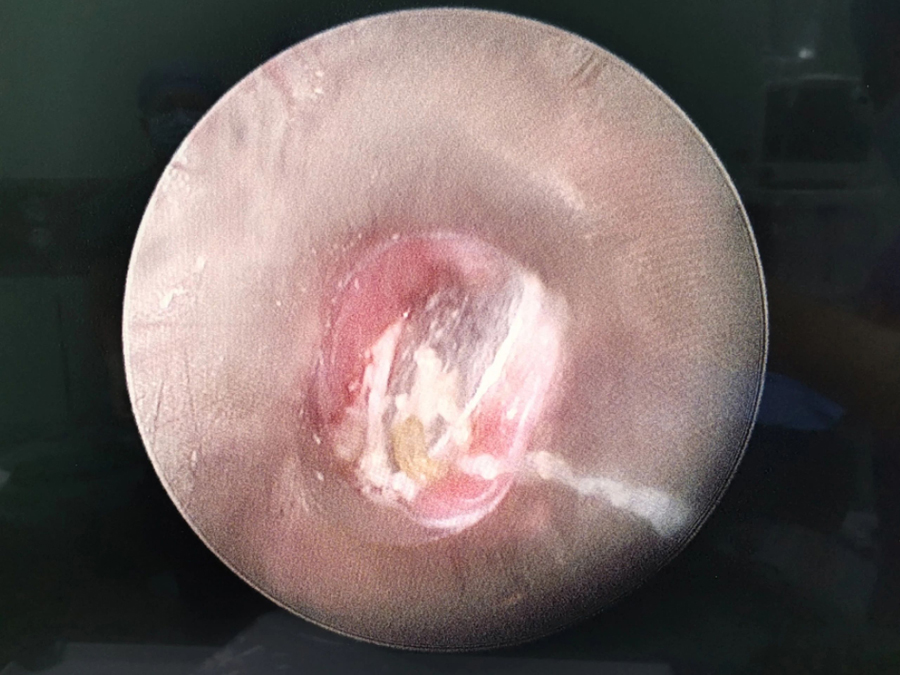

了解了患儿的情况后,国家儿童医学中心、首都医科大学附属北京儿童医院耳鼻喉头颈外科常驻专家、啪啪网 副院长张薇仔细看了患儿的X光片,明确了异物的存在和准确位置。由于异物存留时间长,食道是否有肉芽增生、有无穿孔等情况都不明确,张薇副院长决定采用全麻下通过食道镜直视下行异物取除术。

手术非常顺利,当卡在小强食道入口下方的硬币被取出后,家长才知道,原来导致孩子受罪一个多月的竟是一枚硬币。由于硬币卡在食道内时间太长,被取出时颜色已经发黑。术后,小强不能像其他孩子一样迅速恢复呼吸,而是住进了ICU。原来是由于异物坎顿,食道入口关闭不全,小强进食时总会呛咳,导致反复吸入性肺炎,肺功能明显受损,肺内通气量不足、反复发热,全身身体机能下降,所以不能及时苏醒。不过,经过医务人员进一步治疗后,小强现已康复出院。

小花的情况比小强好一些,硬币被取出后,顺利回到病房,经过两天住院观察和治疗就出院了。